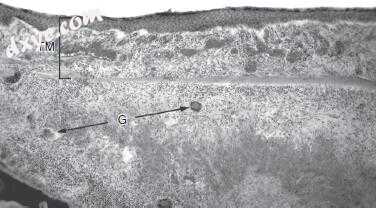

图-7. 图-6中可以看到鼓膜(TM)的放大图。 TM是完整的,但由含有典型的上皮样,圆形和多核巨(G)细胞(×100)的结核肉芽组织严重增厚。

8.jpg